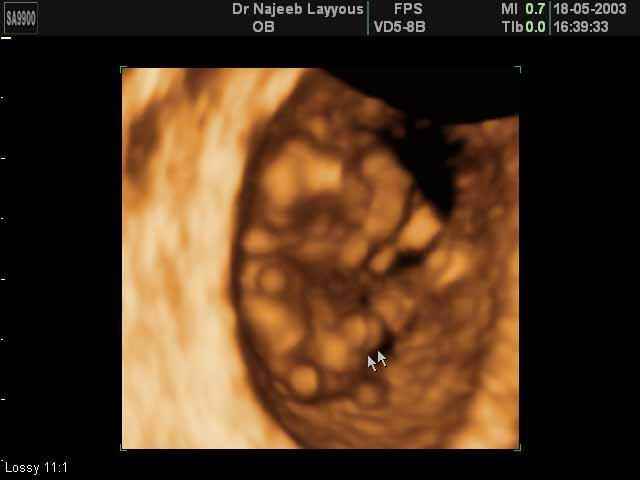

- لقطات فيديو للجنين بجهاز الموجات فوق صوتية رباعي الأبعاد

- صور للجنين في المراحل الأولى من الحمل

- صور لوجه الجنين في داخل الرحم